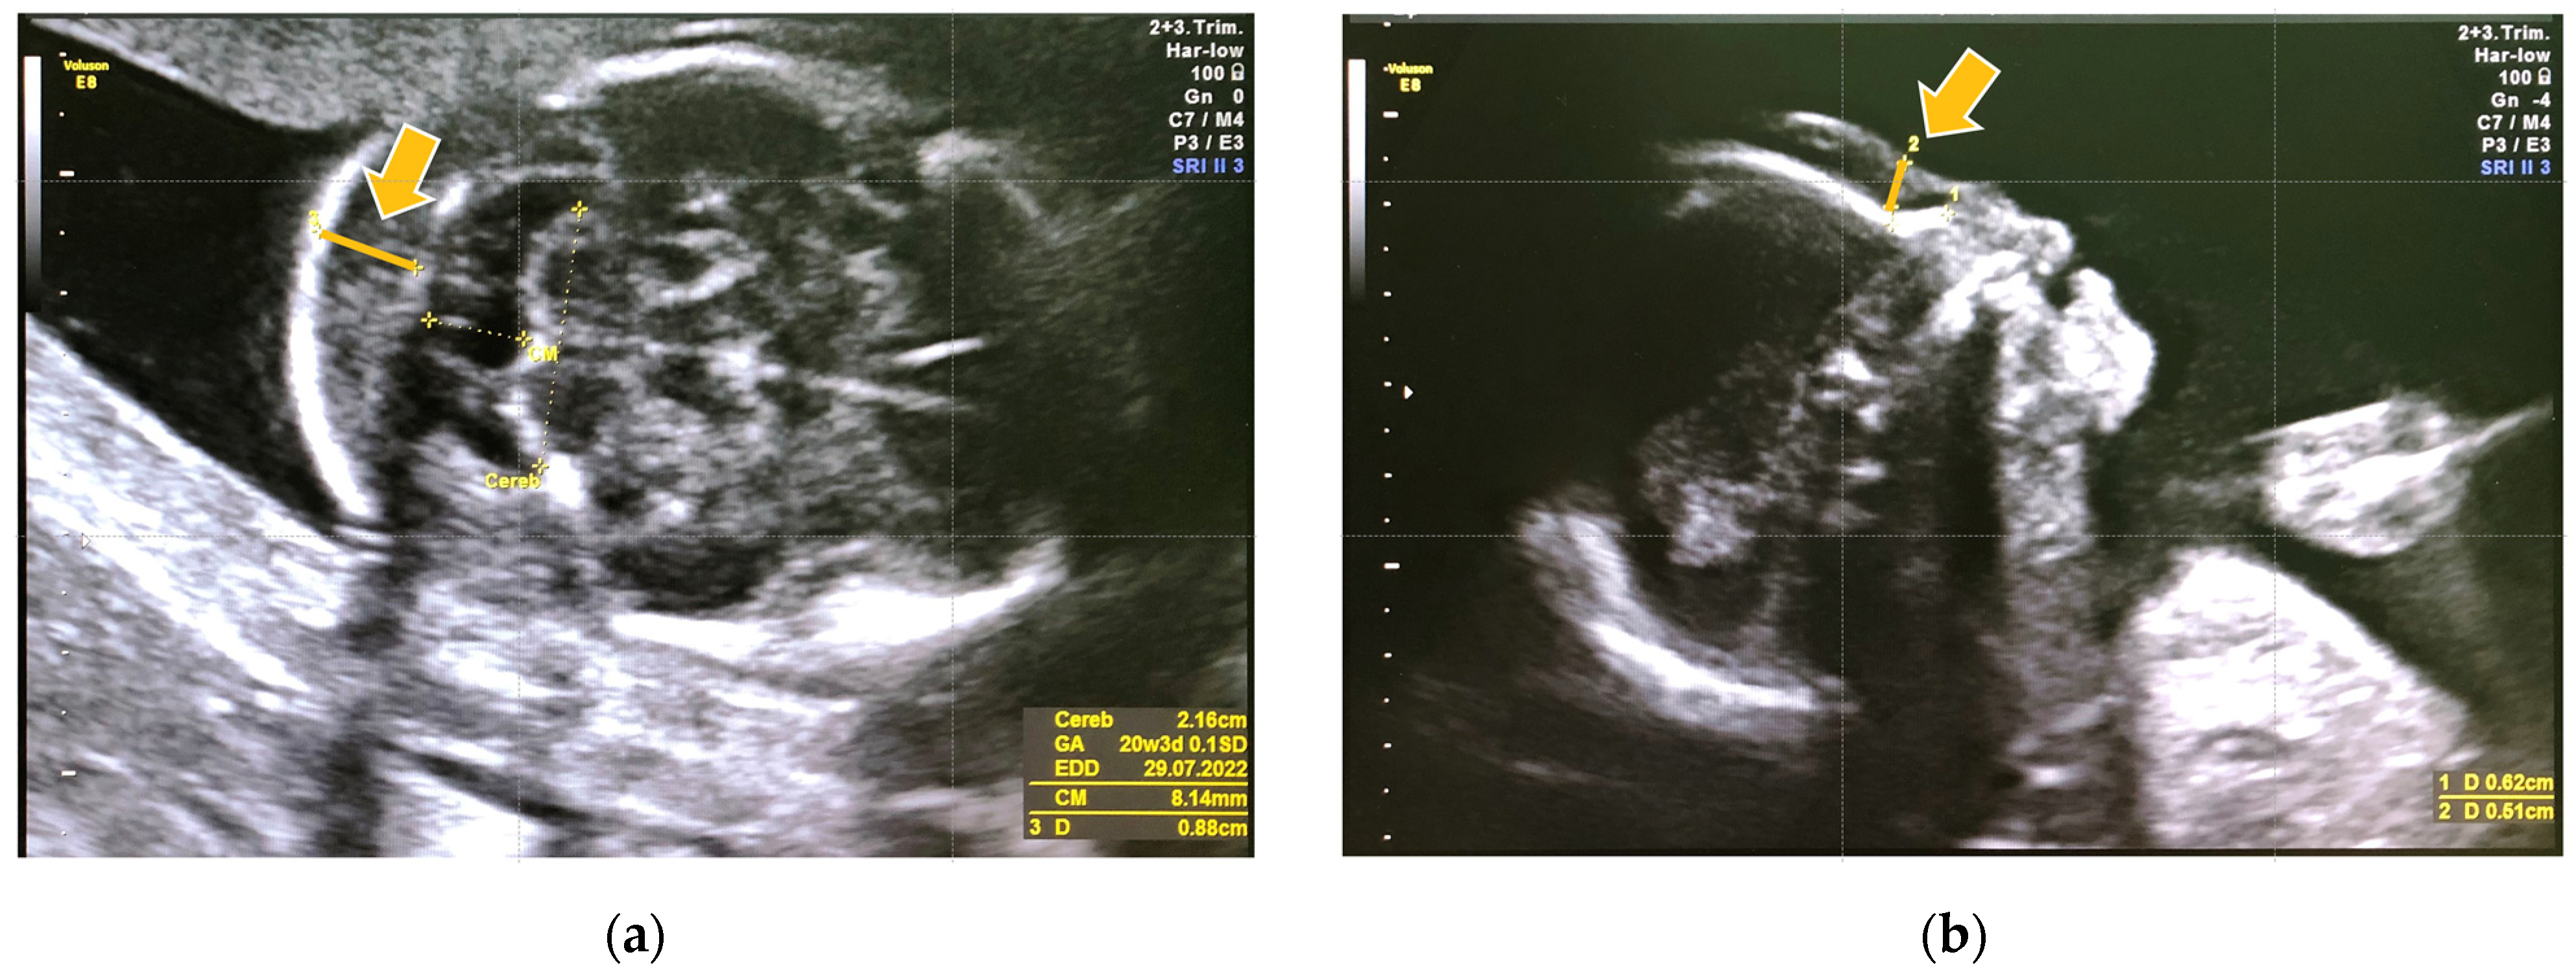

A 23-year-old woman from a Yakut family underwent US in her second trimester (at 20 weeks and 5 days). CFTS showed a low risk for trisomy 21 (Table 1). US revealed an increased thickness of the nuchal fold and prenasal thickness (Figure 2). Genetic counseling was offered due to the abnormal US features.

Figure 2.

Prenatal ultrasonography of case 2 in the second trimester. (a) Nuchal fold thickness is the area of tissue at the back of the fetus (indicated by an arrow). (b) Prenasal thickness is the shortest distance between the anterior edge of the lowest part of the frontal bone and the facial skin anteriorly (indicated by an arrow). Both of them were increased.

In case 1, GT was unavailable due to the unidentified causative variant for MPSPS at that time. As a result, MPSPS remained undetected despite some abnormal US features in the fetus. However, in case 2, abnormal US features were detected during the second trimester, highlighting the significance of identifying such features to prompt suspicion of MPSPS. Increased prenasal thickness and thickness of the nuchal fold may serve as potential US markers requiring further investigation for MPSPS during the second trimester. However, how many MPSPS patients show these specific US findings is yet to be determined due to limited prenatal data.